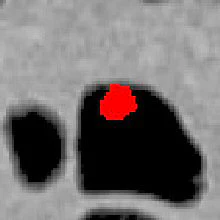

| Above and below: Images from a clinical case demonstrate the density mapping method with CAD. Top, polyp covered by tagging material. Below, polyp is revealed after CT-value correction and density mapping. Third image from top, CAD detection is overlaid on the original image. Bottom, CAD detection overlaid on the corrected and mapped image. |

![]() |